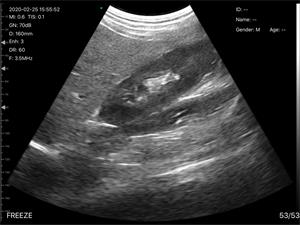

C3无线超声诊断仪

适用对象:

[ 猫、狗、牛、马、老鼠、异宠 ]

数字成像技术,清晰的图像,高性价比

无线连接,操作简单轻便,携带方便